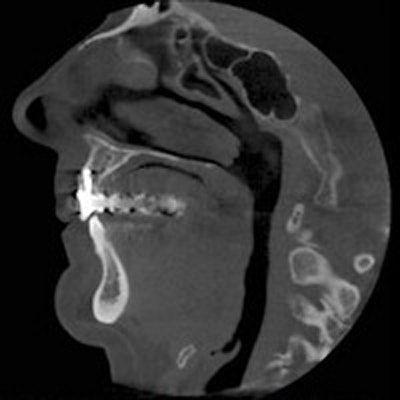

2017 08 09 20 29 13 26 Cbct Thumb 400

There was a time in the not-so-distant past when taking radiographs as part of a dental examination was commonplace. However, with fears about radiation and changing insurance policies, U.S. practices took fewer images in 2016 than in any recent year. Why? Alitta Boechler of Sikka Software looks at the data. Read more.